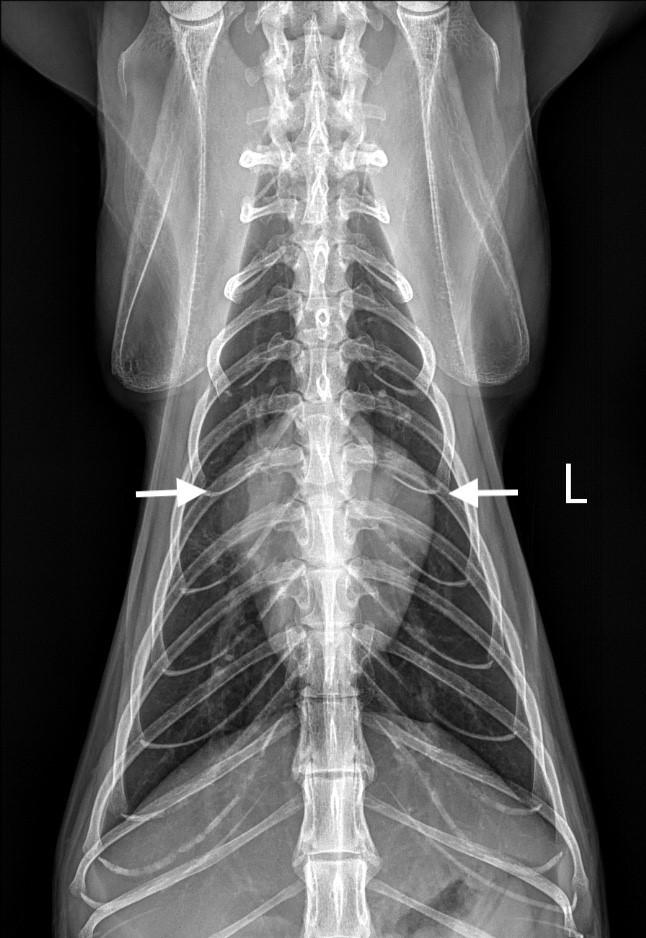

Las cepas de CPV-2 y FPV pueden infectar otros hospedadores (coyotes, lobos, mapaches, panda rojo, hurones, leones, chacales y mangostas)6,10-13 y per manecer en el ambiente más de un año.5,14 El CPV se propaga rápidamente por ruta fecal-oral (transmisión directa) o por exposición oronasal a fómites contami nados con heces (transmisión indirecta). Se replica en la orofaringe, ganglios mesentéricos y timo, pro duciendo viremia 1-5 días tras la exposición. Poste riormente, infecta a las células en rápida división de las criptas del epitelio intestinal, médula ósea, lengua, cavidad oral y miocitos, y otros tejidos (pulmones, hí gado, bazo y riñones) (Fig. 1). El periodo de incuba ción comprende entre 4 y 14 días, precediendo la elimi nación de virus en heces a la sintomatología clínica en el paciente.1,4-6 Durante el destete, los enterocitos de las criptas intestinales tienen un alto índice mitótico debi do a los cambios en la flora bacteriana y la dieta, por lo que son más susceptibles al tropismo vírico.1,2,4-6,15

Figura 1. del parvovirus canino. Figura 2. Diarrea hemorrágica en un paciente canino con parvovirus.

Fisiopatología

yMantenimientocirculaciónde virus Otros órganos: - Corazón - Hígado - Riñones - Pulmones - Cerebro Eliminaciónvirusenheces (3 días post-infección4 semanas) sanguinolentaDiarreaNecrosisvellosidadesintestinales intestinalEpitelio Viremiaensangre Replicación viral en médula ósea1-5 días post-infección Infecciónoral Replicación viral en tejido linfoide (orofaringe mesentéricos,timo)